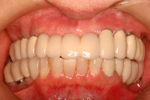

症例 2

① 上の顎・治療前

② 前から見た状態・治療前

③ 上の顎 インプラント後

④ 上の顎。最終的なオールセラミックの歯が入ったところ。

⑤ 上下とも治療の終わった状態。メインテナンスに入ります。

60才代 女性

総額:360万円(税別)

治療期間:約1年

リスク副作用:経年的な骨の吸収。セラミックの破損。